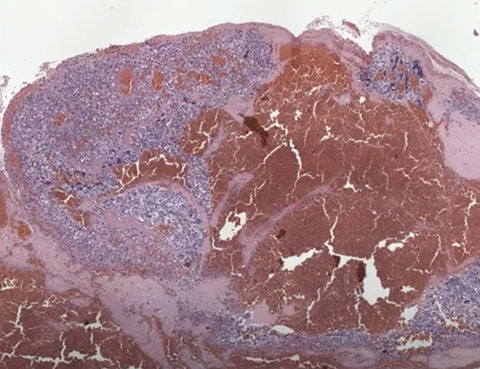

Choriocarcinoma

Comes from trophoblastic cells after pregnancy (either normal or abnormal)

- 1/2 assoc c moles (esp complete moles [1/40 chance])

- 1/4 from spontaneous abortions

- 1/4 from normal pregs (1/100,000)

- smalll % from ectopic pregs or teratomas (~2%)

- risk factor: being Nigerian, type A blood

- present c bleeding, foul-smelling discharge, very inc hCG (~18k) - which causes rxns in other organs (Arias-Stella rxn, breast duct hyperplasia, etc etc)

Gross: soft, fleshy hemorrhagic and necrotic, can be big or small

- sample the blood clot, especially at the periphery

Micro: Biphasic (all are cytokeratin and GATA3 +)

- cytotrophoblasts (CT, small, round mononucleated cells c clear cytoplasm) and intermediate trophoblasts (rIT, edder cytoplasm, has morphology of other 2 types??)

- syncytiotrophoblasts (ST, multinucleated) c variable atypia, pleomorphism, hyperchromasia, big nucleoli

- lots o mits, invades down to sm muscle and into vessels

- since doesn't make vessels, see lots of necrosis with only viable tumor found around periphery

- no villi are present

IHC: (+) CK, CEA

- int trophoblasts: (+) HLA-G, hPL, Mel-CAM (CD146)

- cytotrophoblasts: (+) p63

- syncytiotrophoblasts: (+) hCG, weak aPL

- mononucleate cells have high Ki67 (>90%)

- negative PLAP

Genes: Diploid (and diandric in CHM)

Tx: Chemo very successful

- monitor hCG

Px: Will survive if given chemo and tumor just in uterus; drops to 8/10 survival if pt has mets

- Aggressive, rapidly invades and mets (to lung, vag, brain, liver, kidney, bowel; rarely mets to embryo (kiddo)

- worse if >39 yo mom, higher hCG, blood group B, larger size, mets

- better if lots of inflam bwt tumor and stroma